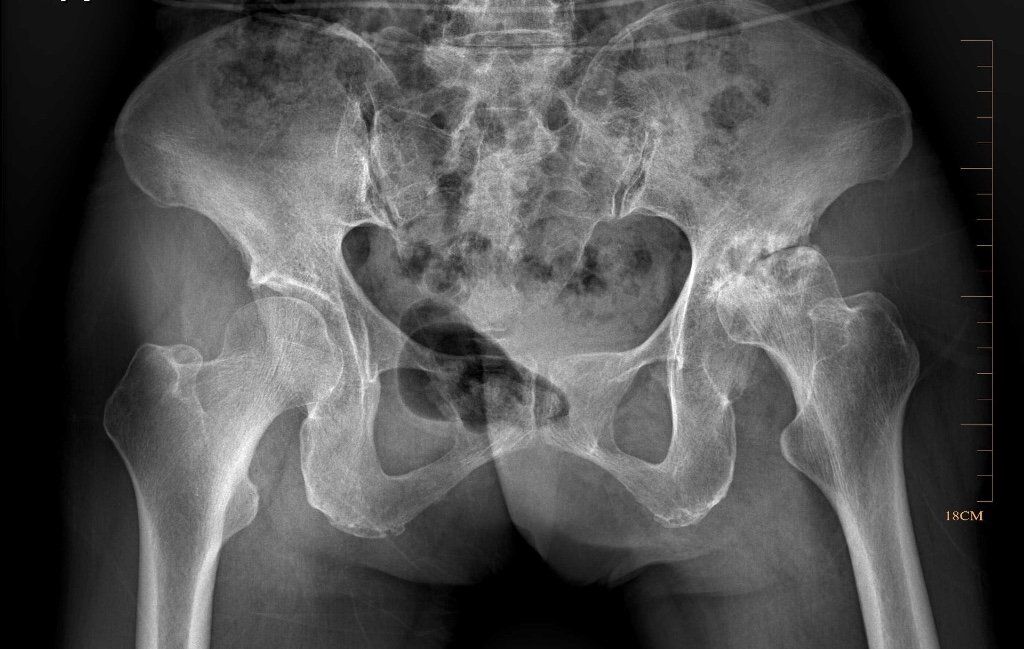

L’objectif de cette intervention est de remplacer l’articulation coxo-fémorale (articulation entre le bassin et la partie supérieure du fémur) par une articulation en métal plastique ou céramique.

Elle se compose d’une cupule métallique (titane ou inox) mise en place dans le bassin et d’une tige mise en place dans le fémur, et d’une interface qui reconstruit l’articulation proprement dite que l’on appelle le couple de frottement. Ce dernier peut être une articulation céramique – céramique, métal-polyéthylène ou céramique-polyéthylène selon les cas.